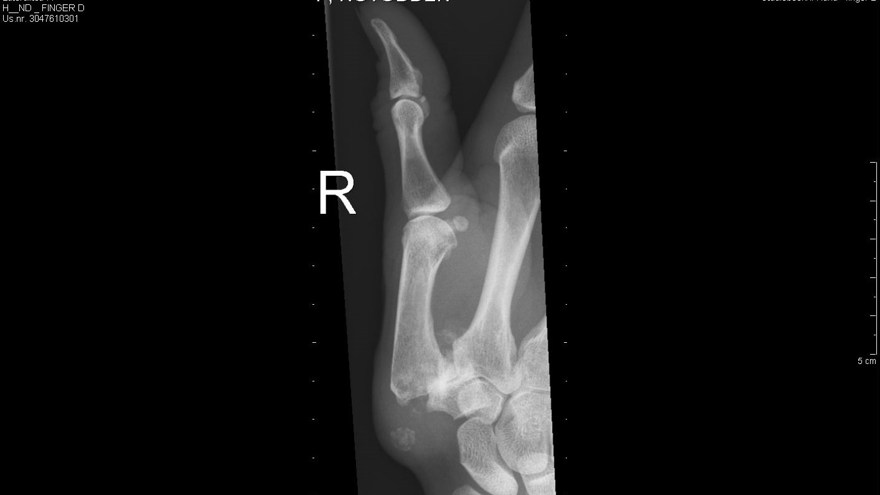

Den vanligaste lokalisationen av primär artros i handen är i tummens carpometacarpalled (CMC 1) – tumbasartros, med eller utan samtidigt engagemang av leden mellan scaphoideum och trapezium (STT-leden).

Tillståndet är 8-10 ggr vanligare hos kvinnor och debuterar vanligen mellan 45-50 år. Kliniskt finner man krepitationer i den engagerade leden samt smärta (”Grinding-test”) vid provokation i form av axial kompression och rotation av tummens bas. Vid engagemang av STT-leden har patienten smärta i handleden vid radialdeviation. Diagnosen fastställs radiologiskt.